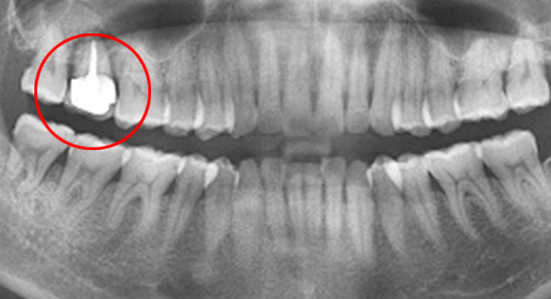

치조골 손상이 심해 발치를 하고 임플란트를 해야 하는 상황

인접치아로 발치된 공간을 메움

46세 남성환자로 상악동 거상술과 임플란트 진단을 받은 상태로 내원. 치조골이 2/3이상 오염되어 살릴 수 없어 발치를 진행, 인접치아를 움직여 발치 된 공간을 닫는 교정치료를 시행하였습니다.